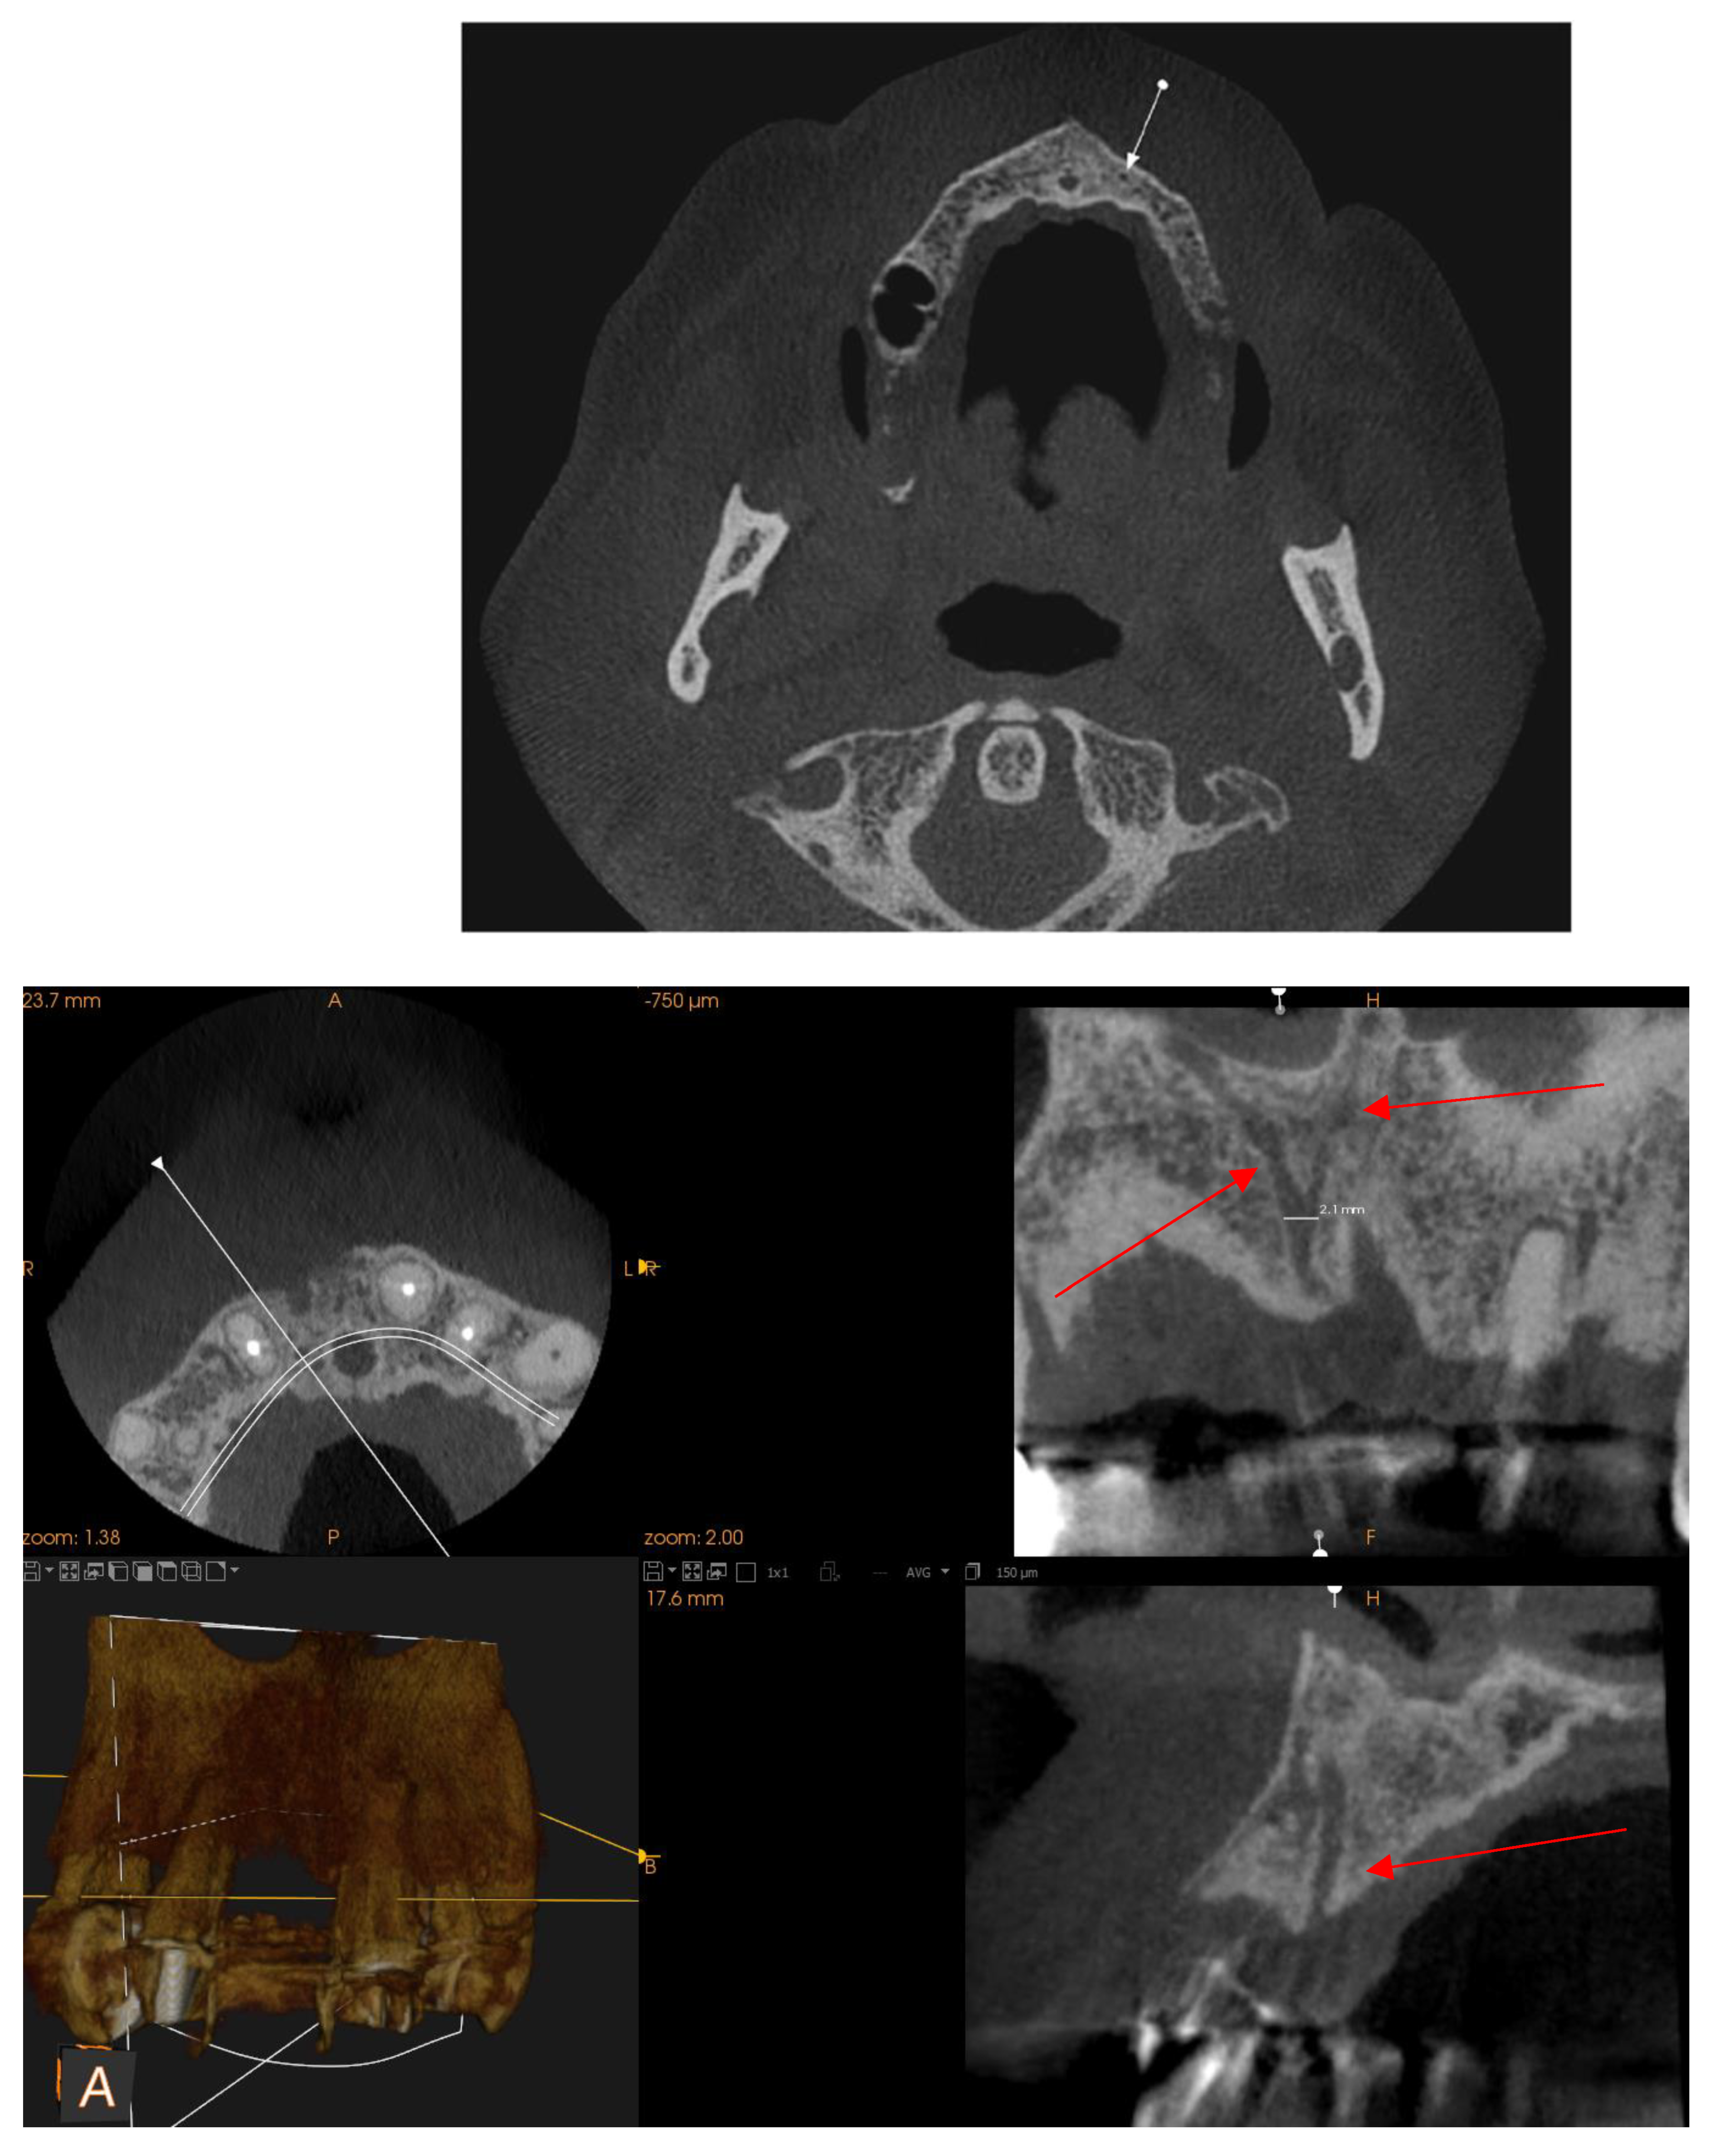

Posterior superior alveolar artery

Mentonian Hole